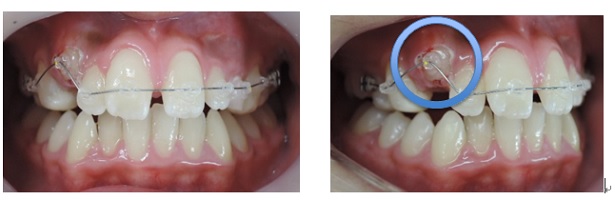

出来るだけ見えにくい矯正装置(ブラケット)を上下顎に装着して歯並びを整えていきます。矯正装置を装着後3日から7日ぐらいまでの間は歯が動きだすために軽い痛みを感じることがあります。

また、矯正装置が口腔内という敏感なところに装着される事で異物感を感じます。そのために本能的に装置を取ってしまいたいと考えて、当日から翌日位は矯正装置が脱落する事が多いです。

次にMEAW(マルチループ)を利用する事で咬み合わせの高さや前歯の傾斜を整えていきます。

また、MEAW(マルチループ)はゴムを24時間使用する事で最大の効果を発揮することが出来ます。

当院では簡易なMEAW(マルチループ)を使用する事で上下の前歯部をより綺麗な歯並びにしていきます。

この時にも24時間使用するゴムが大切です。